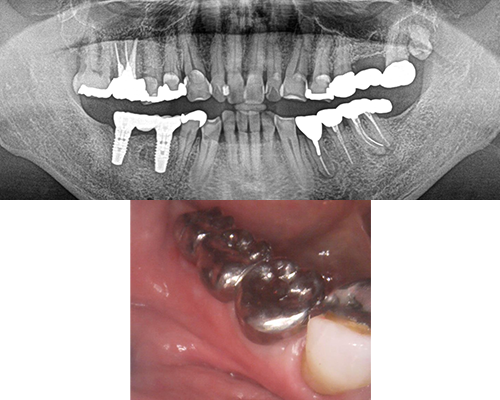

| 施術内容 | 前歯は虫歯や歯の動揺が大きく、奥歯も虫歯や歯根破折のため保存困難。左上1本以外抜歯し、骨が足りない部位は骨増生を行いインプラント治療へ。通常の入れ歯と違いインプラントを固定源とするため、安定性がかなり高いです。(治療期間中は入れ歯を使用) |

|---|---|

| 治療期間 | 約1年半(抜歯後治癒期間含) |

| 治療費 | 約280万円(プラスチック前装冠) |

| 副作用・リスク | インプラント治療は手術を伴います。腫れや痛みが少なくなるよう努力をしておりますが、多少の腫れや痛みが出ます。しかし、痛み止めで抑えられる程度ですのでご安心ください。 |

※表示は全て税込表示です。